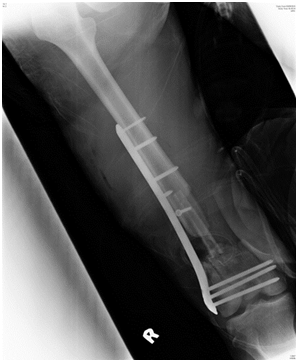

Postoperative radiograph showed acceptable fracture alignment with autogenous fibular graft inside the medullary canal (Figures 2A & 2B).

The patient was allowed active mobilization of the knee joint after surgery but weight bearing on the injured limb was strictly not allowed. The patient was allowed partial weight bear and full weight bear at 4 and 6 months respectively. The fracture achieved radiological union at 6 months after internal fixation and bone grafting (Figure 3A & 3B). Patient was able to ambulate independently without aid. Right lower limb however was shorter by 2cm but patient did not have any functional complain and this can be equalized with a shoe lift. Right thigh muscles were atrophic. Passive range of motion of the right knee was 0 to 130 degrees while active range of motion was 10 to 120 degrees. Ankle joint was stable. Fibular graft donor site healed with no complication.

Figure 3a Figure 3A(Right) Radiograph of the right femur, AP view, six months after surgery showing fracture site union with incorporation of the fibula graft.

Figure 3b (Left) Radiograph of the right femur, lateral view, six months after surgery showing fracture site union with incorporation of the fibula graft